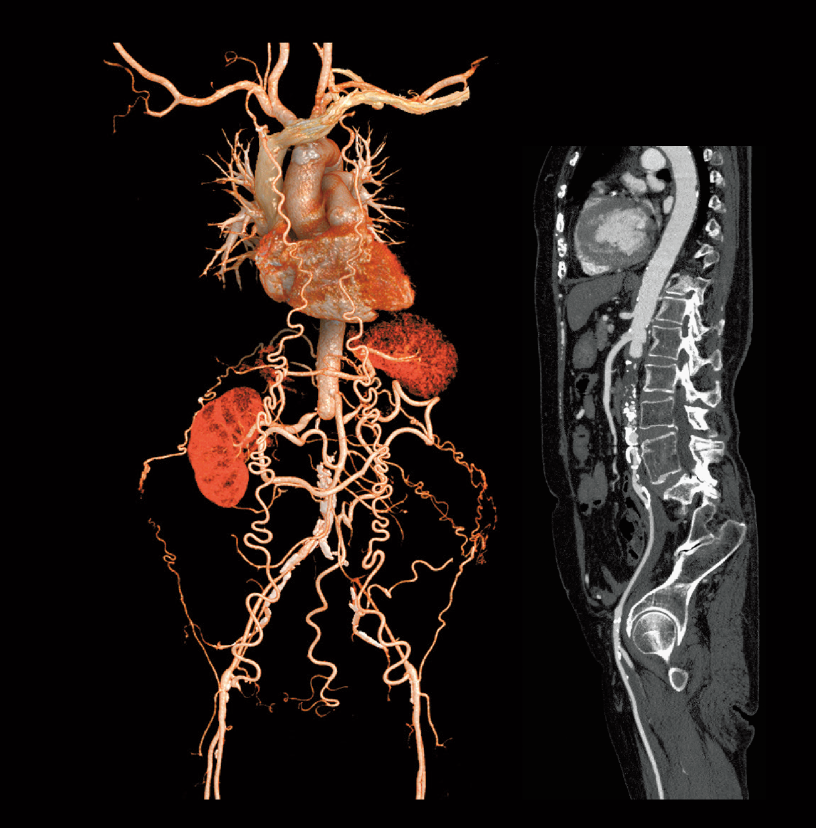

Abdominal aortic occlusion

Intraoperative oxygen desaturation (Left)

Left common iliac artery occlusion (Right)

- * Images other than axia images were processed by the 3D image analysis system SYNAPSE 3D.